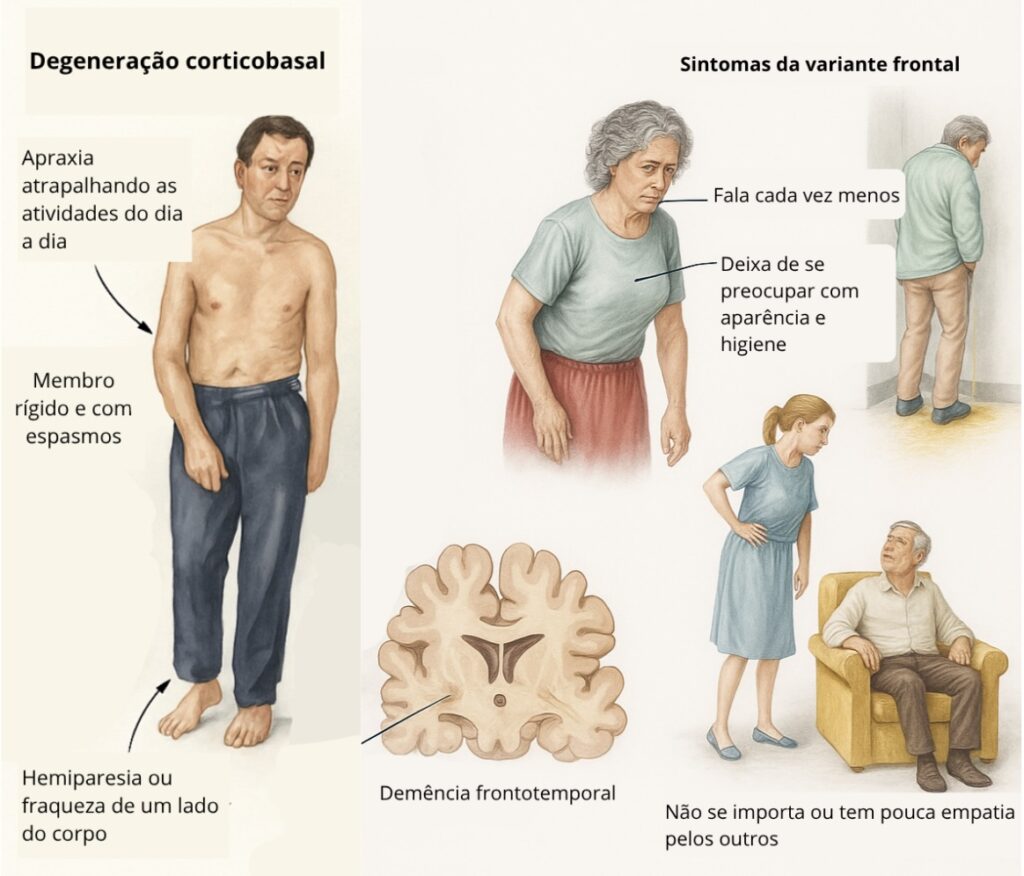

3. Degeneração Corticobasal (DCB)

- Começa frequentemente com um lado do corpo mais afetado.

- Além dos sintomas motores, pode haver dificuldades cognitivas, movimentos involuntários, sensação de que um braço não obedece e parece “estranho”.